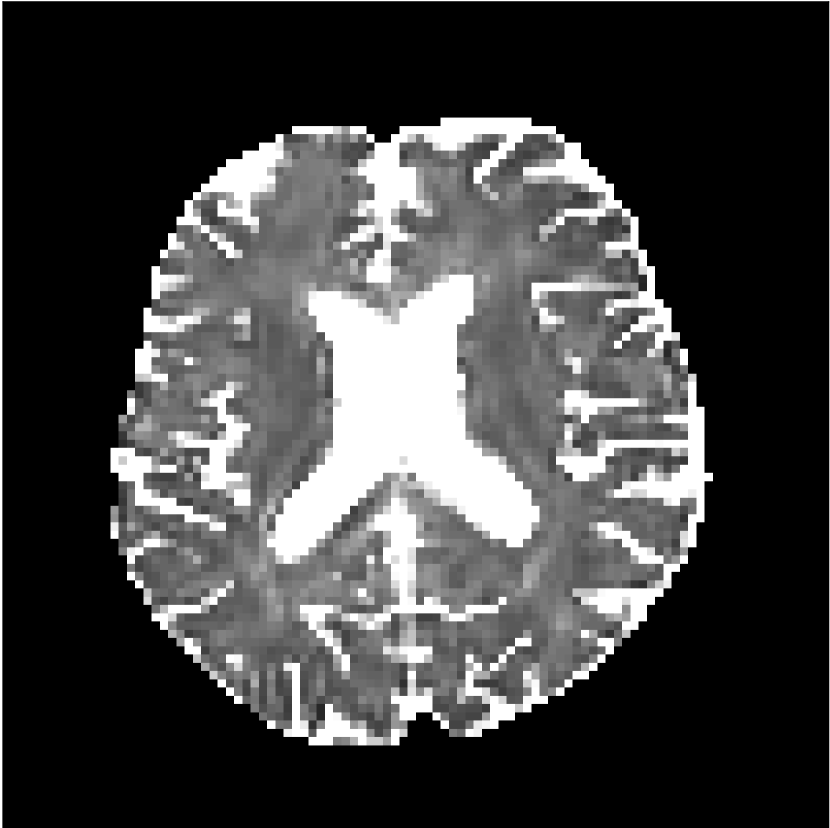

Figure 9 shows parameter maps for the different methods without partial Fourier (No PF) and with 5/8ths partial Fourier (5/8 PF). Mean diffusivities calculated from the raw DWI data (Raw) show notable noise and Gibbs ringing artifacts, while this is substantially removed with the state-of-the-art (SoA) method. However, the state-of-the-art method begins to lose its ability to compensate for the Gibbs ringing and resolution loss when partial Fourier is utilized in the acquisition. The effects of partial Fourier increases are primarily evident in the enlargement of the lateral ventricles and the presence of black lines in the vicinity of the lateral ventricles. The MCNN model is able to compensate somewhat for the ringing effects, but begins to introduce substantial artifacts at the 5/8ths partial Fourier factor, whereas the CCNN model continues to give high-quality mean parameter maps across all PF factors.

Raw

SoA

MCNN

Standard PF

CCNN

s/mm2

No PF

MD, m2/ms

5/8 PF

FA

MK

Similar trends are observed in the other diffusion parameter maps.